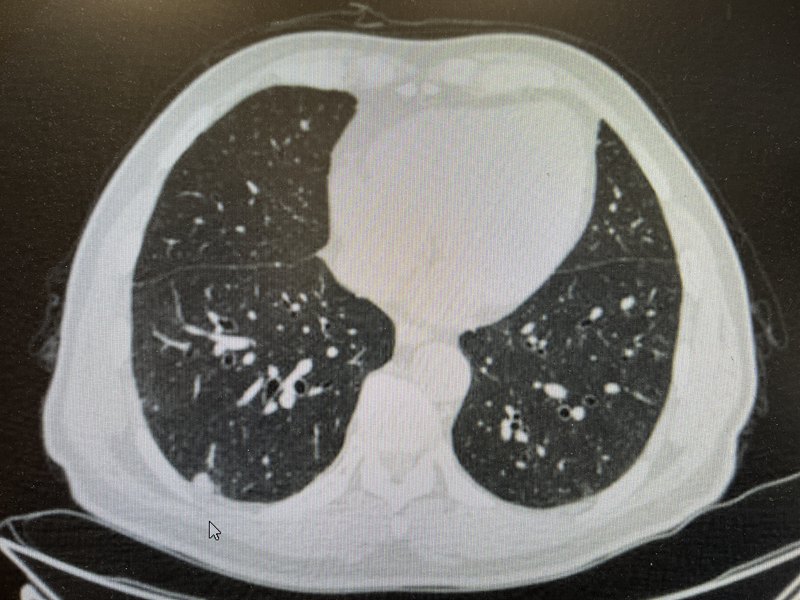

????在第1篇中,我們初步解釋了磨玻璃結(jié)節(jié)的影像表現(xiàn)和病理特征。在這一篇中,我們將簡要介紹實性結(jié)節(jié)的影像與病理,了解為什么說實性結(jié)節(jié)“易于走極端”。????與磨玻璃結(jié)節(jié)相比,實性結(jié)節(jié)密度更高,與人體軟組織的密度接近,可以遮蓋血管影和支氣管影,因此在CT縱隔窗上有所顯示。????在介紹磨玻璃結(jié)節(jié)的時候,我們提到了“實性成分比例”的概念。對于磨玻璃結(jié)節(jié),當(dāng)其發(fā)展到實性成分比例100%的時候,它就成為了實性結(jié)節(jié)。????盡管相當(dāng)一部分的實性結(jié)節(jié),最終證實為良性(例如錯構(gòu)瘤、肉芽腫、硬化性血管瘤等),但是仍有一部分實性結(jié)節(jié),最終證實為惡性。并且,實性結(jié)節(jié),一旦診斷為肺惡性腫瘤,基本上就是浸潤性癌。簡單講,就是說,當(dāng)CT上發(fā)現(xiàn)實性結(jié)節(jié)時,如果手術(shù)病理證實為惡性,那么往往已經(jīng)存在浸潤,而不是原位、不是微浸潤。????這就是為什么說實性結(jié)節(jié)“易于走極端”。????那么,發(fā)現(xiàn)實性結(jié)節(jié),病人應(yīng)該怎么處理?????首先,建議胸外科、影像科、核醫(yī)學(xué)科等多學(xué)科閱片、判讀。這一過程中,需要結(jié)合年齡、性別、吸煙史、肺部疾病,以及其他檢驗、檢查,綜合判斷。????其次,病人自己如何做一個初步的心理建設(shè)和預(yù)期呢?可以從三個方面出發(fā):第一、實性結(jié)節(jié)的直徑多少?一般來講,越是小的結(jié)節(jié),越是良性概率大,6mm以下的,多數(shù)建議隨訪,更不用說3、4mm的。第二、有無惡性腫瘤病史,尤其是有無肺癌、腸癌等的病史?一般來講,沒有惡性腫瘤病史的,往往不考慮轉(zhuǎn)移性癌(畢竟概率太低)。第三、是否已經(jīng)觀察了一段時間?一般來講,實性結(jié)節(jié),尤其是8~10mm的實性結(jié)節(jié),很難直接做出判斷。這時候,變化趨勢就是重要的診斷標準。????筆者最近處理了多例實性結(jié)節(jié),謹以2例,提供參考。(病例1)右肺實性結(jié)節(jié),2019年體檢發(fā)現(xiàn),最初當(dāng)?shù)蒯t(yī)院考慮良性可能大。后未及時復(fù)查。2023年CT提示結(jié)節(jié)較前增大。遂來我院就診??焖俨±碜C實“浸潤性腺癌”。正式病理顯示:浸潤性腺癌,低分化,篩狀為主,侵犯胸膜,可見氣腔播散、脈管癌栓,未見神經(jīng)侵犯;支氣管切緣陰性;清掃各組淋巴結(jié)均為陰性。(病例2)左肺實性結(jié)節(jié),初次閱片時,測得結(jié)節(jié)密度較高,似乎不像肺癌。但是,病人有過隨訪,對比當(dāng)?shù)蒯t(yī)院CT,發(fā)現(xiàn)較前明顯增大。遂收入我科,快速病理證實“浸潤性癌,傾向腺癌。正式病理顯示:浸潤性腺癌,低分化,實體型,未見胸膜侵犯,可見氣腔播散,未見脈管癌栓、神經(jīng)侵犯;支氣管切緣陰性;清掃各組淋巴結(jié)均為陰性。????綜上,實性結(jié)節(jié)容易走極端,需要高度重視。

雙肺多發(fā)小結(jié)節(jié)真的束手無策嗎?